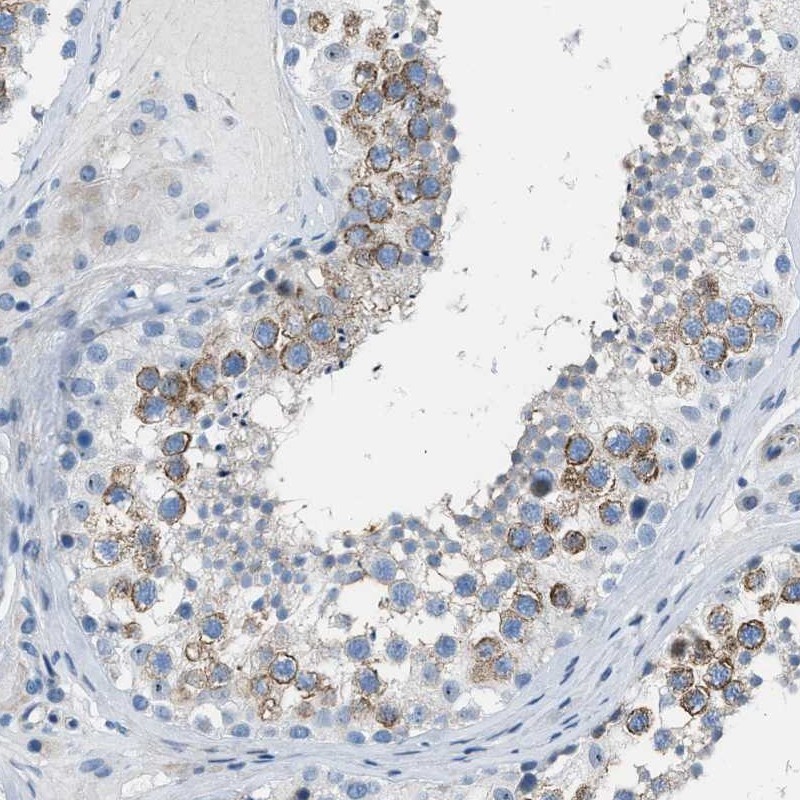

Immunohistochemical staining of human testis shows strong cytoplasmic positivity in seminiferous ducts.